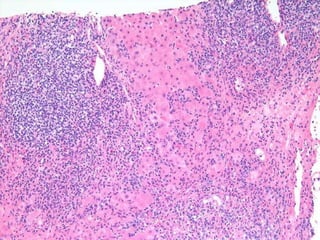

BS09-10453 55 yo, female.  Clinical history:  Elevated ALT/AST. Viral serologies negative.

BS09-10453:  Dx: Chronic hepatitis, with severe activity (bridging necrosis) and portal fibrosis, ? autoimmune hepatitis vs. drug/toxin mediated injury. Corresponds to: Modified Ishak stage 1/4 Metavir F1

BS09-10453 55 yo,female. Clinical history: Elevated ALT/AST. Viral serologies negative.

BS09-10453: Dx:Chronic hepatitis, with severe activity (bridging necrosis) and portal fibrosis, ? autoimmune hepatitis vs. drug/toxin mediated injury. Corresponds to: Modified Ishak stage 1/4 Metavir F1